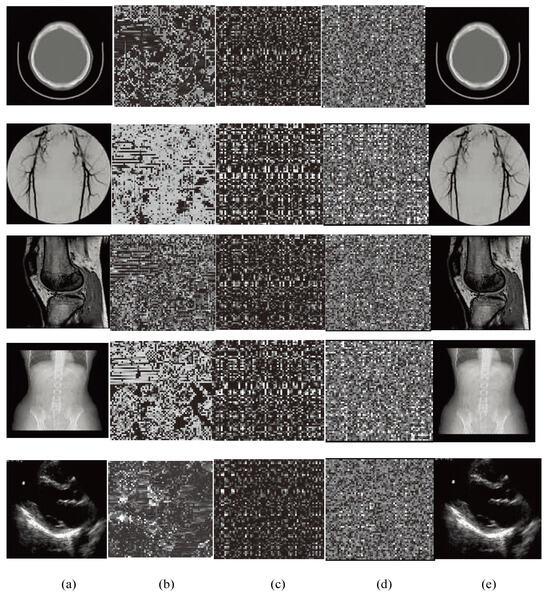

4.1. Perceptual Effect

4.7. Encryption Process Discussion

| Image No. | (a) | (b) | (c) | (d) | (e) |

|---|---|---|---|---|---|

| 1 | 5.7615 | 7.3832 | 7.4264 | 7.9056 | 5.7615 |

| 2 | 5.7336 | 7.4245 | 7.3967 | 7.6865 | 5.7336 |

| 3 | 6.7269 | 7.2968 | 7.2965 | 7.8589 | 6.7269 |

| 4 | 6.3829 | 7.4510 | 7.2910 | 7.6912 | 6.3829 |

| 5 | 5.8691 | 7.6023 | 7.3703 | 7.8359 | 5.8619 |